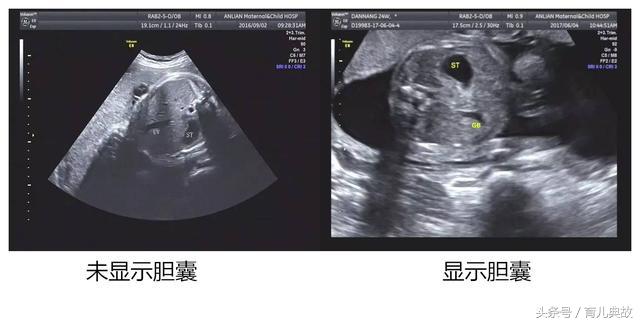

孕28周到了正常做超声检查的时间,原以为这次检查都会像以前一样平安度过,可是现实却把脸打的啪啪响,原来医生在检查时发现腹中宝宝没有胆囊,很可能是胆道闭锁。

无缘无故查出这种毛病,这消息对夫妻俩无疑是晴天霹雳。夫妻俩根本不相信会是这样的结果,可去了多加医院检查,可每次给出的答案都是如此:“没有显示胆囊,可能是胆道闭锁”。